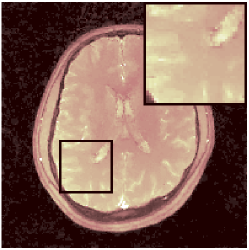

VI-F MRFResnet’s consistency with DM

Further to section VI-C validations, we compare parametric maps computed by DM and MRFResnet for the in-vitro and in-vivo scans, where the LRTV algorithm was applied for TSMI reconstruction. Results are summarised in Table III and for the in-vivo 2D spiral scan is illustrated in Figure 9. We observe very small differences in parametric maps (Table III) and particularly for the regions corresponding to white and grey matters predictions are highly consistent with each other (Figure 9).

. diff T1(s) diff T2 (s) diff PD (a.u.)